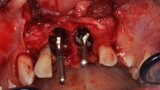

Ryc. 9_Miejsce biorcze po wytworzeniu łoża.